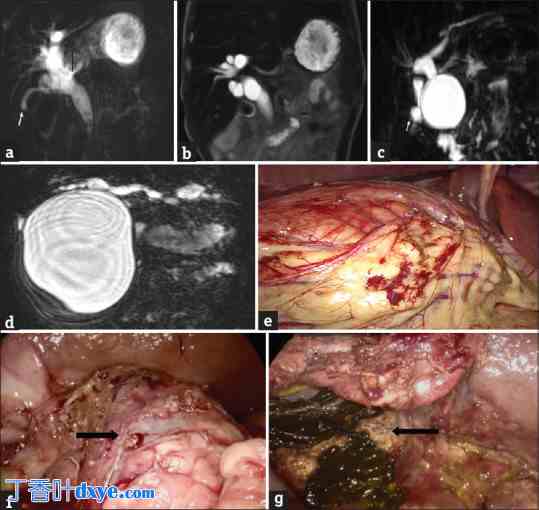

所有患者均接受了磁共振胰胆管造影 (MRCP) 检查,以清晰描绘肝胆解剖结构[图 1a-c]。并采集了常规血象、肝功能检查和凝血酶原时间。

图 1.

1.jpg

(a) 1 岁儿童的磁共振胆胰管造影 (MRCP) 图像,单次激发厚层二维 MRCP 图像,胆囊收缩较小(白色箭头);(b) 冠状位 T2W 图像,显示 1 型胆总管囊肿 (CDC);(c) 7 个月大儿童的三维最大强度投影 MRCP 图像,显示 1 型 CDC。白色箭头表示胆囊;(d) MRCP 图像,显示 16 cm × 10 cm 的巨型囊肿;(e) 巨型 CDC 的术中图像;(f) CDC(黑色箭头)和十二指肠重复囊肿的术中图像;(g) 进一步解剖囊肿,显示双叶 CDC(黑色箭头表示 CDC 的叶)